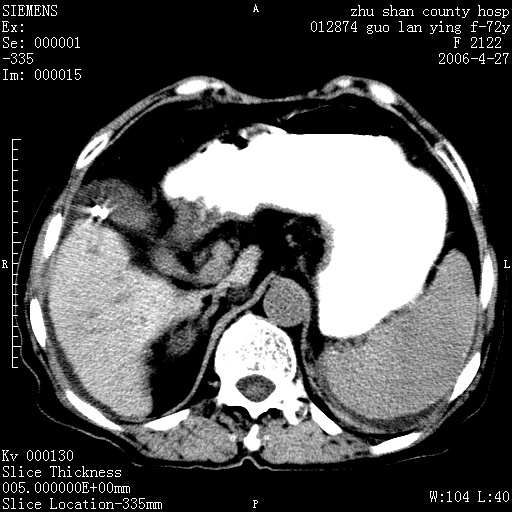

病人 女性 72岁 b超要求ct检查!

平扫所见:胆囊区两点壮高密度影,灶周有伪影{请问楼主患者有手术病史?}。肝实质内未见明显异常{建议强化或mri}.腹腔有少量积液,脾明显增大.右肾形态似不规则?

腹腔内示积液征,脾脏略增大,肝脏由于运动伪影较多,影响观察,内未见明显高密度区,胆囊内示两处高密度结石。胃窦部壁轻度增厚。另外,肝脏的前缘似有游历气体。不知病人的临床如何?有必要做胃的检查,还有,看看骨窗是否有腹腔游离气体还是肠管影响的。

如果b超对肝脏有怀疑,肝脏的增强扫描还是尽量去做。

肝脏缩小,脾脏增大,肝脾外缘及胆囊窝液性密度影,肝脾ct值正常,胆囊区见两个类圆形高密度影,下腔静脉前方类圆形软组织密度影为肝脏岛叶,胃幽门区见软组织密度影,十二指肠钡剂充盈不好.

1:腹水2:胆囊结石3肝硬化?(不确定,请结合临床)4幽门区占位?(建议胃肠透视)

肝硬化,脾大,少量腹水

肝硬化、脾肿大,腹水,胆囊区高密度影(结石或异物),是否有外伤史

肝硬化、腹水、脾大,胆囊结石可以肯定。只是肝右叶两个低密度有必要增强确定一下;排除小肝癌。

谢谢牟教授在百忙之中还认真的点评我的帖子!也谢谢大家的鼎力相助,此病人是我们医院护理部主任的母亲!病人以前无特别不舒适!昨天b超后发现有问题!做ct的目的在于排除肝内占位性病变,此病人以前无手术外伤史.